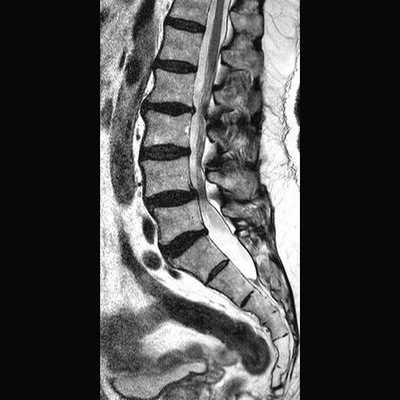

В первом учреждении использовался локатор на весь позвоночник, Т1-, Т2-, STIR-взвешенные изображения в сагиттальной плоскости, Т2-взвешенные изображения в коронарной плоскости (рис. 1). Исследование выполнялось на аппарате Рhilips Intera 1.5Т. Технические параметры импульсных последовательностей представлены в таблице. Технические параметры импульсных последовательностей для МРТ поясничного отдела позвоночника

Рис. 1. МРТ поясничного отдела позвоночника, позиционирование плоскостей. а — позиционирование локатора на весь позвоночник; б — позиционирование сагиттальной плоскости.